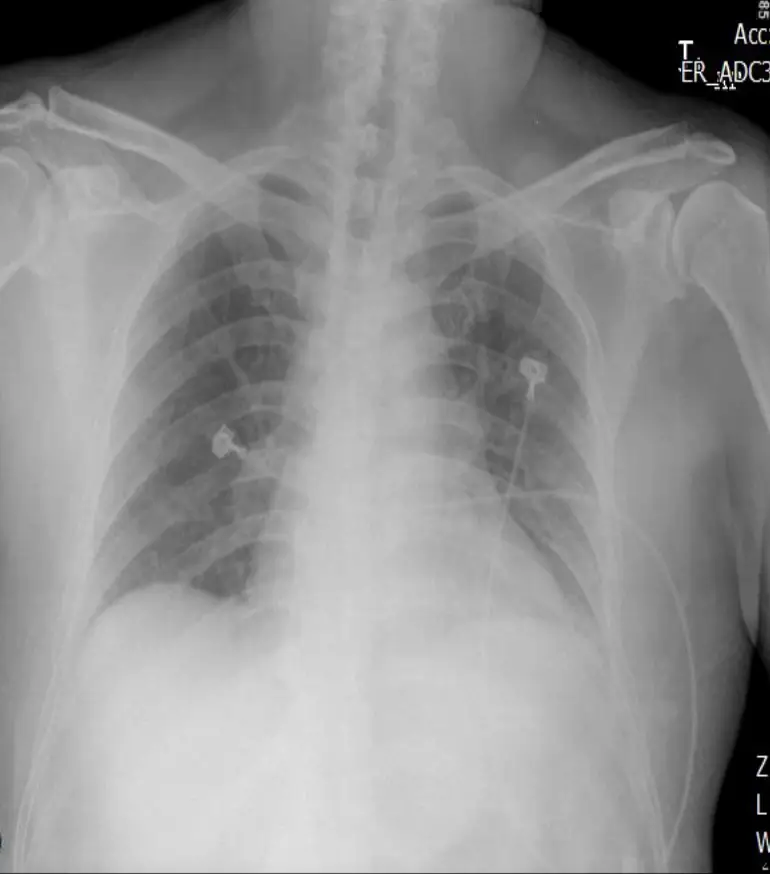

胸部X光:

- 可見肺血管回流增多、Kerley B 線及雙側胸膜下輕度浸潤,提示急性肺水腫(肺充血),合併SBP 86 mmHg,極可能已進入心源性休克早期。

結合以上,病人屬於高危STEMI合併低血壓及初期肺水腫,必須謹慎用藥,避免任何進一步降低血壓或心輸出量的治療。